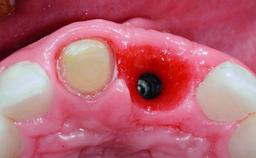

Replacement of a Missing Upper Left Central Incisor, Late Placement of an RC Bone Level Implant and Adjacent Tooth Restoration

A healthy 38-year-old male patient was referred for replacement of a failing tooth-supported cantilever fixed dental prosthesis on teeth 11 and 21. The patient reported a history of trauma at 13 years of age that had resulted in the subsequent loss of tooth 11, as well as endodontic treatment of the adjacent abutment tooth 21. A metal-ceramic cantilever fixed dental prosthesis replacing tooth 11 had been provided by his general dentist several years after the loss of the tooth, with tooth 21 as the sole abutment. At the time of initial presentation, this restoration had been in service for over 20 years.

Bone Augmentation | Horizontal|Simultaneous |

Augmentation Materials | Xenogenous|Membrane |